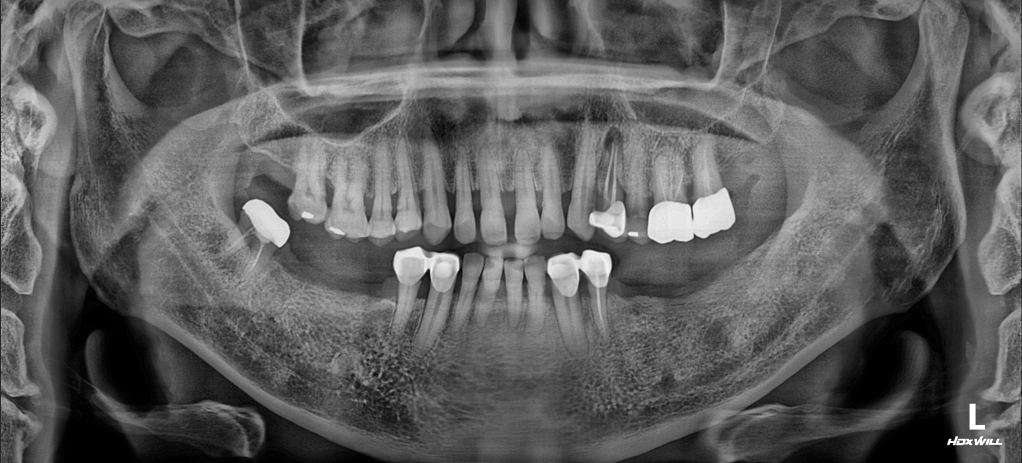

OPG - BEFORE

A male patient in his 50s presented with significant functional and aesthetic concerns stemming from a long-term collapsed occlusion. Due to years of wearing dentures with an insufficient vertical dimension (low VDO), the patient experienced a "domino effect" of oral health issues:

• Mandibular Retrusion & Deep Bite: The lack of posterior height caused the mandible to shift backward, creating a pathological deep bite.

• Anterior Pathological Migration: Without stable posterior "stops," excessive occlusal forces were transferred to the anterior segment, leading to labial flaring and the development of wide diastemas (spacing).

1. Phase 1: Posterior Stabilization: Dental implants were strategically placed in the posterior regions. These units served as the primary anchors for the new VDO, effectively "unlocking" the mandible from its retruded position.